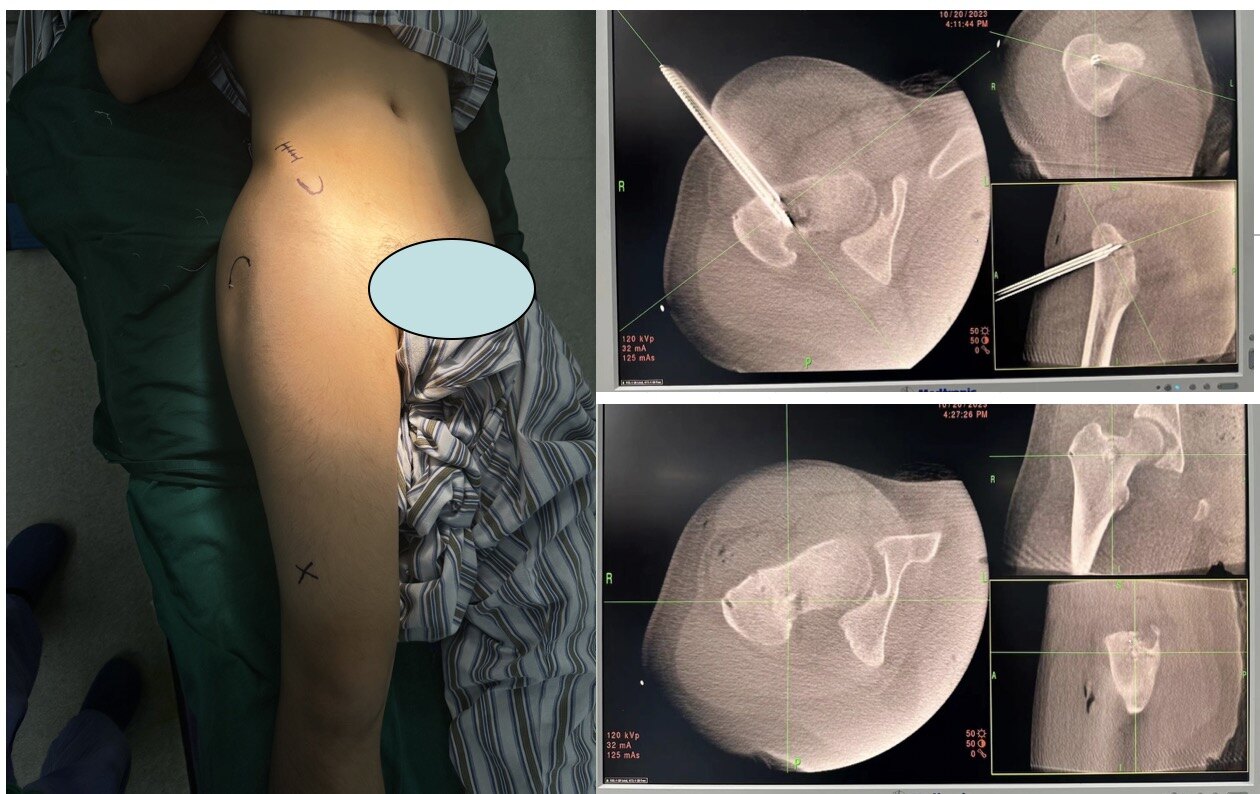

股骨近端良性腫瘤的導航下微創(chuàng)治療

男性,13歲,右側臀部疼痛3年余,檢查提示股骨近端良性腫瘤可能,輾轉多家醫(yī)院就診,均被告知需要進行切開刮除植骨手術。后于蔡鄭東主任好大夫問診,被診斷為骨樣骨瘤,建議微創(chuàng)下消融治療。結合患者家屬意愿綜合考慮后,定于導航通道下行右側股骨近端腫瘤消融+通道植骨術,術后患者恢復順利,術后一個月恢復正常。術后病理提示為骨樣骨瘤。

左冬青醫(yī)生的科普號2023年11月21日448